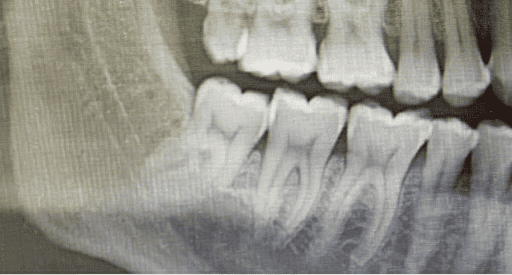

While comprehensive benchmarks exist for evaluating editing models on natural images Lin et al. (2015); Huang et al. (2023); Xia et al. (2021), their adaptation to medical images remains challenging. Here, even minor alterations can carry significant clinical meaning, demanding high editing precision, semantic fidelity, and anatomical correctness. Text-guided medical image editing holds substantial clinical potential, as it could highlight lesions in CT scans Guo et al. (2023), simulate surgical outcomes Huang et al. (2025), or generate personalized teaching materials Lee et al. (2024). Such applications promise direct benefits to diagnosis, treatment optimization Ma (2025), and training Zhang et al. (2024a). Despite the versatility of current models, they often fail at clinically meaningful transformations that are intuitive to general physicians or even non-experts. For example, InstructPix2Pix Brooks et al. (2023a) can successfully handle prompts such as “Add a missing key on a piano keyboard” but fails on similar medical prompts such as “Add a missing tooth in this dental image” (see Fig. 1). Notably, this failure cannot be resolved by adjusting the text or image guidance scales Brooks et al. (2023b) (see Fig. 7), where the text guidance scale controls the classifier-free guidance weight for the text prompt, and the image guidance scale controls the conditioning strength on the input image during denoising. This underscores the difficulty of transferring such models to domains that require fine-grained anatomical understanding and specialized domain knowledge Kazerouni et al. (2022); Ayana et al. (2024).

Figure 7 illustrates the limitations of controlling text and image guidance scales in diffusion-based image editing. Specifically, for the task of “adding a missing tooth,” varying these scales fails to yield a satisfactory result when using the InstructPix2Pix model. While increasing the text guidance scale emphasizes the semantic prompt, and higher image guidance preserves visual fidelity to the original image, neither direction successfully produces the desired anatomical modification. This outcome suggests that simply tuning global guidance weights is insufficient for achieving fine-grained, localized edits in medical or detail-critical domains. As shown in Figure 7, the generated outputs either omit the new tooth entirely or introduce unnatural artifacts, underscoring the need for more controllable and spatially-aware editing approaches.

Edit Prompt: “Remove the wisdom teeth.”

Description of Expected Change: “Panoramic dental radiograph: Wisdom teeth in the upper and lower jaws were removed, resulting in a post-surgical appearance with space in the alveolar bone where the teeth previously resided.”